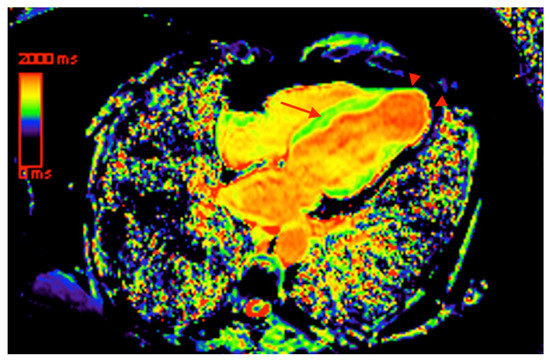

- Torreão, J.A.; Ianni, B.M.; Mady, C.; Naia, E.; Rassi, C.H.; Nomura, C.; Parga, J.R.; Avila, L.F.; Ramires, J.A.; Kalil-Filho, R. Myocardial tissue characterization in Chagas’ heart disease by cardiovascular magnetic resonance. J. Cardiovasc. Magn. Reson. 2015, 17, 97. [Google Scholar] [CrossRef]

- Kammerlander, A.A.; Marzluf, B.A.; Zotter-Tufaro, C.; Aschauer, S.; Duca, F.; Bachmann, A.; Knechtelsdorfer, K.; Wiesinger, M.; Pfaffenberger, S.; Greiser, A. T1 mapping by CMR imaging: From histological validation to clinical implication. JACC Cardiovasc. Imaging 2016, 9, 14–23. [Google Scholar] [CrossRef] [PubMed]